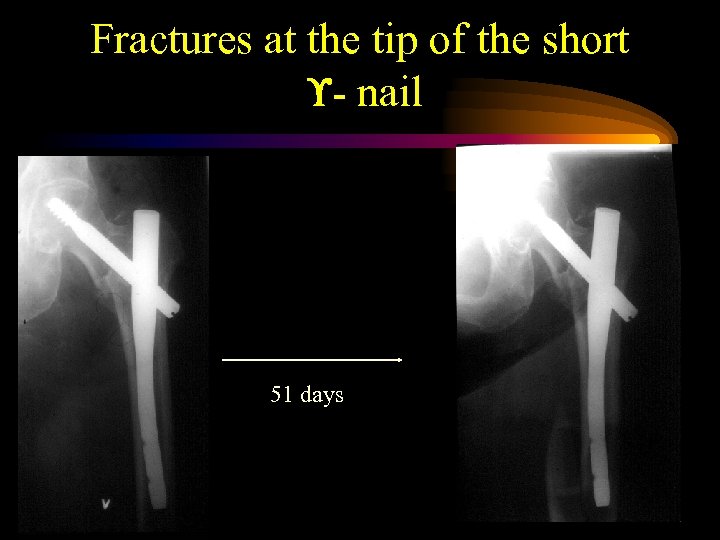

Fractures at the tip of the short - nail 51 days

Fractures at the tip of the short - nail 51 days

Fractures at the tip of the nail • Aune et al. Acta Orthop Scand 1994; 65 (2): 127 -30: HCS vs. Gamma nail 378 patients: 5. 6 % • Madsen et al: J Orthop Trauma 1998 Vol. 12. No 4 50 patients 2. 9% • Osnes et al. Norw. proceedings 1998: 379 patients 5. 3%

Fractures at the tip of the nail • Aune et al. Acta Orthop Scand 1994; 65 (2): 127 -30: HCS vs. Gamma nail 378 patients: 5. 6 % • Madsen et al: J Orthop Trauma 1998 Vol. 12. No 4 50 patients 2. 9% • Osnes et al. Norw. proceedings 1998: 379 patients 5. 3%